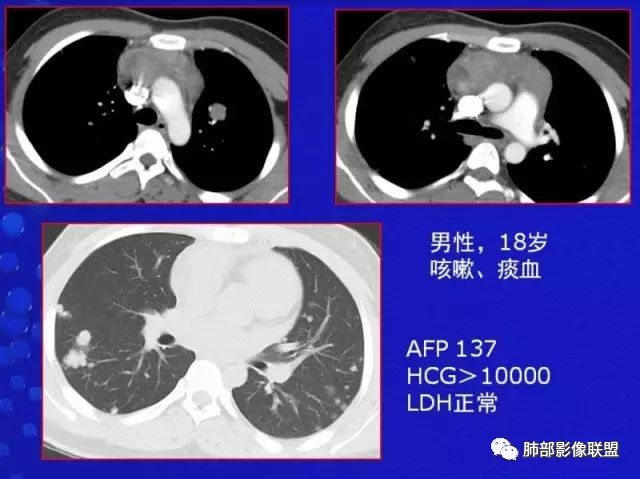

是高度恶性生殖细胞肿瘤,卵黄囊细胞是唯一产生AFP的细胞,所以AFP升高是卵黄囊瘤或含有卵黄囊成份的生殖细胞肿瘤最重要的特征,其中卵黄囊瘤一般大于1000ug/L;影像表现肿块体积往往较大,易坏死囊变,易侵犯周围结构及转移。

4、绒毛膜癌

纵隔原发性绒毛癌病人几乎为男性,也是高度恶性生殖细胞肿瘤,血、尿β-HCG升高是绒毛膜癌的一个特征,男性乳房发育,影像表现呈分叶状巨大肿块,亦出血坏死,富血供病变,易侵犯血管,所以早期容易出血转移,最常累及的器官为肺。

男性,12岁,绒癌伴双肺转移

是一种起源于胚胎期多功能造血干细胞的未分化癌,可单独或作为混合型纵隔生殖细胞肿瘤出血,与卵黄囊瘤并发在青少年中较为常见,以青少年男性多见,HCG明显升高,AFP升高,影像表现也是体积巨大,易坏死囊变及钙化,呈浸润性生长,易转移;